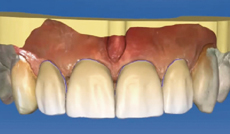

在使用者進行數位印模的同時

軟體將自動為你分析備牙區域狀況

包括空間、平整度、倒凹程度…等資訊;

使用者將更有效的掌握修復體的品質

提高其臨床的成功率